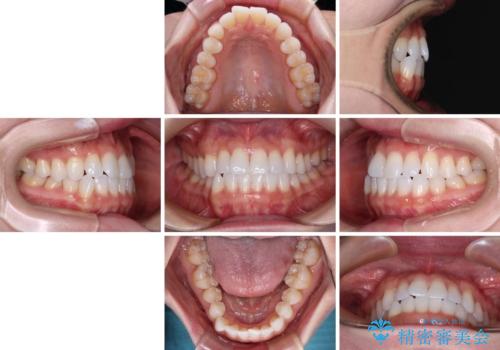

- 上下前歯の叢生を気にして来院された患者様です。

インビザラインでの治療を希望されていて、デコボコの程度が中等度であり、安価なパッケージにて対応可能と判断されたため、インビザライン・モデレートを用いて矯正治療を行うこととしました。

インビザライン・モデレートは、製作できるアライナーの枚数に制限があるため、移動可能な量に限りがあるものの、インビザライン・ライトよりも枚数が多いため、幅広い症例に対応可能です。